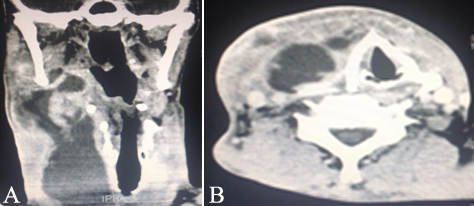

During admission, the anamnesis did not reveal systemic pathologies, chronic use of medical drugs or potential medical allergies. Yet clinically, an evident edema was detected in the right submandibular region presenting a central floating area (Figure 1). Infectious cavities in the right and left submandibular, pterygomandibular and pharyngeal regions were observed through computed tomography scans (Figure 1). Laboratory blood tests revealed levels of hematocrit (36.2%), hemoglobin (11.9 g/dL); leukocytes (24500/mm3), gram-negative rods (8%), C-reactive protein (18.15 mg/L) and erythrocyte sedimentation rate (20 mm/h) (Table 1). Based on the clinical, radiographic and laboratory examinations, the patient was diagnosed with an odontogenic deep neck abscess.

Figure 2.Preoperative computed tomography in coronal (A) and axial (B) views, revealing infectious cavities in the deep neck.

Santos Gorjón et al9 performed a large descriptive review of cases of deep neck infections, reporting that most of the patients exhibited involvement of peritonsillar and submandibular areas. In detail, the authors also revealed that submandibular abscesses were associated with odontogenic infections in 60% of the adult patients. Similarly in the presented case, tomographic exams revealed the involvement of multiple deep neck infectious cavities, mainly in the submandibular and pharyngeal spaces. Another large-population survey was performed by Boscolo-Rizzo et al,2 revealing that neck swelling and throat pain were reported by 93.2% and 56.2% of the patients with deep neck infections, respectively. Similarly, these clinical findings were also the main evidence observed in the present case. Additionally, the authors reported that 15 patients had Ludwig’s Angina, characterizing diffuse gangrenous cellulitis of the submandibular and sublingual spaces.2 On the other hand, in our case the patient did not exhibit involvement of the sublingual space.